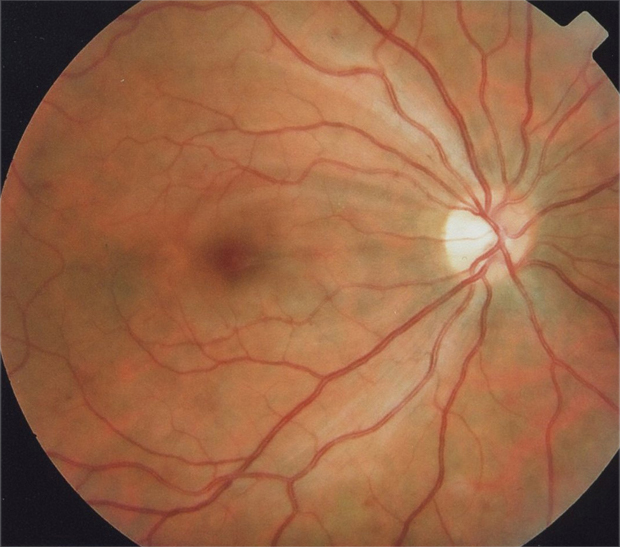

Caso 1

Historia Clínica

Mujer de 32 años con cefalea después de liposucción con anestesia general 10 días antes de consultar

AV: OD 0,15 OI 0,30 con corrección

Midriasis media

IDX

Retinopatía de Purtcher Secundaria a Embolismo Graso después de Liposucción

Retinopatía de Purtcher

Angiopatía retiniana traumática con manchas algodonosas, extravasación linfática después de aumento de presión intracraniana.

- Bilateral, 20/200 a CD, alteración de la capa de fibras nerviosas, atrofía disco óptico.

- Angiografía: teñido arterial, escape capilar, más tardíamente, no perfusion arteriolar y venular con teñido de las paredes vasculares y dilatación venosa.